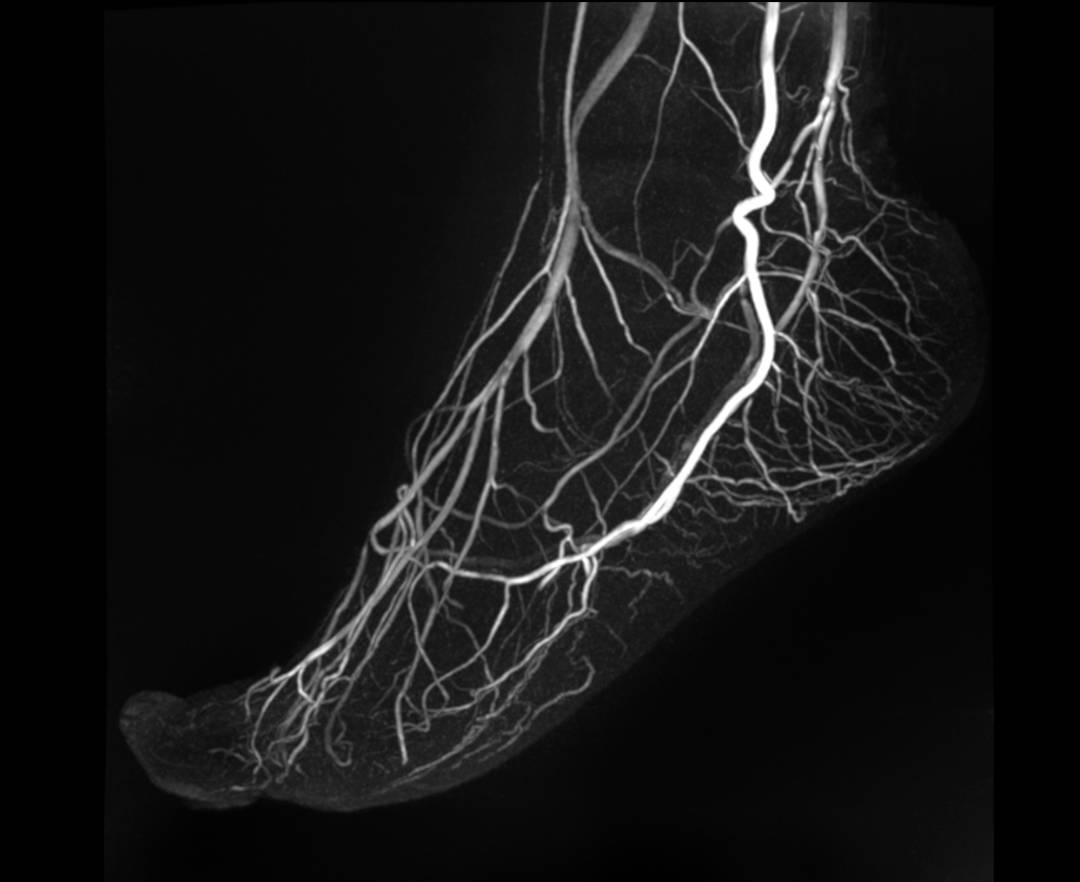

FOOT MRA